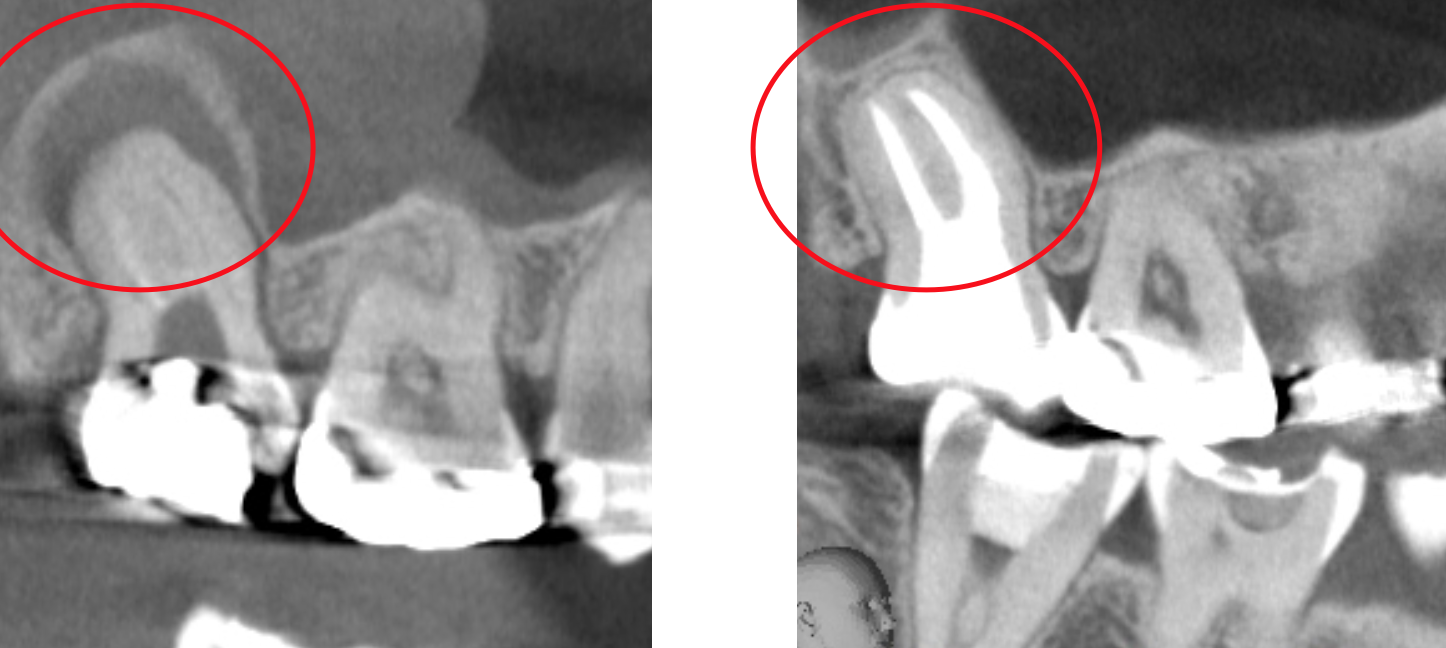

歯科用CTとは一般の医療用CTを歯科治療用に特化した装置です。

当院ではこの歯科用CTを使用して三次元で歯の構造を把握します。

任意の角度や位置から歯・顎骨を確認することもできるので治療の精度が大幅に向上します。